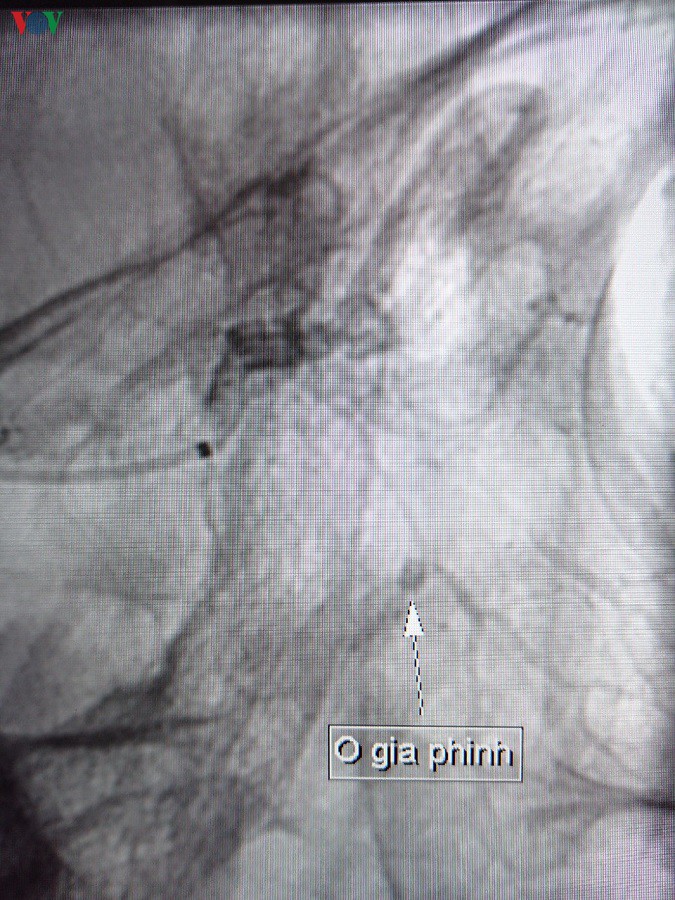

Hình ảnh trước can thiệp

Đến sáng 19-3, mũi bệnh nhân tiếp tục rỉ máu qua bấc mũi trước, bệnh nhân được hội chẩn: chảy máu mũi chưa rõ nguyên nhân tái phát nhiều lần. Tại đây, qua hội chẩn chuyên khoa với các bác sĩ khoa Can thiệp mạch máu, bệnh nhân có chỉ định chụp và can thiệp mạch máu mũi số hóa nền (DSA).